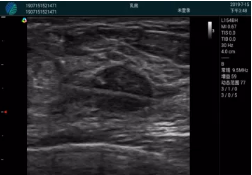

M20查看:囊內(nèi)回聲均勻,邊界清晰,囊壁光滑

M20引導(dǎo)抽吸術(shù)后囊腫消失,原區(qū)域空腔形成,脂肪層與腺體層架構(gòu)發(fā)生改變

超聲以操作簡單、定位準(zhǔn)確、實(shí)時顯像、費(fèi)用低廉等優(yōu)勢,而成為麥默通乳腺活檢治療乳腺腫塊最常見的引導(dǎo)手段,已逐步在各大醫(yī)院開展此類手術(shù)。

2、超聲的可視化操作,能準(zhǔn)確的顯示病灶的位置、最大徑,選擇合適的刀具,決定切口的位置和方向,避開血管、減少出血危險(xiǎn)并實(shí)時觀察乳腺病灶的切割情況,避免造成腫塊組織殘留